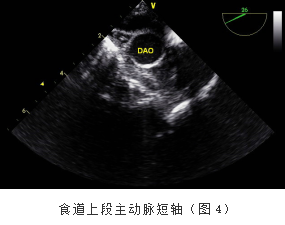

1.食道上段(图4):距门齿15cm-20cm,主动脉弓长轴观、主动脉弓短轴观等。